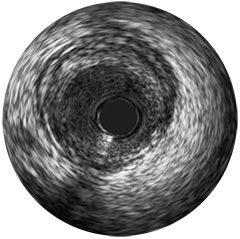

Figura 3

Digital IVUS imaging

Presentamos la nueva plataforma de aplicaciones intervencionistas Philips IntraSight, en la que la imagen, la fisiología, el corregistro* y el software se unen para facilitar una atención óptima del paciente. IntraSight ofrece un conjunto completo de modalidades clínicamente probadas, como la iFR/FFR, la IVUS y el corregistro* para simplificar las intervenciones complejas, acelerar los procedimientos rutinarios y proporcionar una mejor atención al paciente.